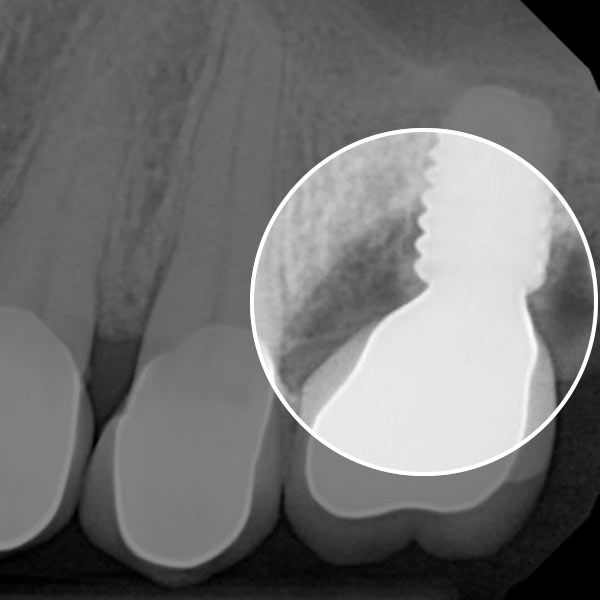

When the tissue around a dental implant becomes inflamed, the post can loosen, threatening the stability of your restoration and your smile.

The LAPIP™ protocol uses advanced laser technology to eliminate infection around the implant and encourage regrowth of soft tissue and bone.

See the Difference LAPIP CAN MAKE

Prevent Implant Failure AND PROTECT YOUR ORAL HEALTH

As you heal, the stem cells from your bone naturally promote tissue regeneration. This encourages your tissue to reattach to the implant post and form a more stable connection.

Peri-implantitis is a serious condition which can threaten the stability of your smile. The best way to find out if you qualify for the innovative LAPIP protocol is to schedule an appointment with a dentist.